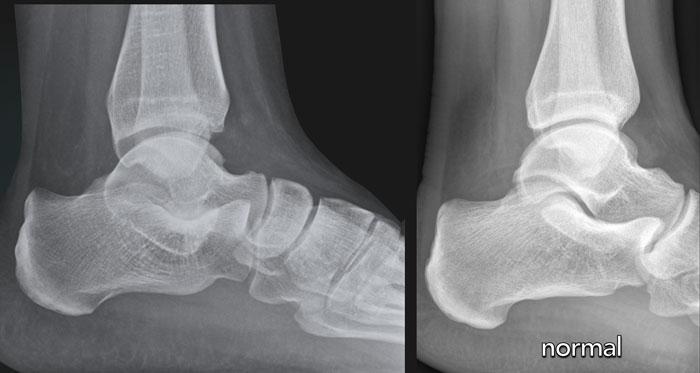

case 2 – chronic pain post ankle sprains

The findings are:

- mỏm trước xương gót kéo dài khớp với xương thuyền.

- the diagnosis is calcaneonavicular coalition.

Xương gót và xương thuyền thường không khớp với nhau.

Trong trường hợp liên kết xương, có thể thấy một cầu xương nối liền hai xương này.

Compare to the normal situation.

Với liên kết xơ hoặc sụn, các xương nằm gần nhau, cả hai đều có bề mặt không đều, và phần trước trong của xương gót bất thường bị giãn rộng hoặc phẳng dẹt.

Trên phim X-quang tư thế bên, sự kéo dài của phần lưng trước xương gót có thể mô phỏng hình ảnh mũi con thú ăn kiến.

Thiểu sản xương sên đôi khi được quan sát thấy trong liên kết gót-thuyền.

Trên CT, chúng ta thấy sự hợp nhất giữa xương gót và xương thuyền.

CT cho thấy xơ cứng xương và các nang dưới sụn như là dấu hiệu của ‘ma sát’ do khớp tân tạo.

MRI cho thấy phù tủy xương như là dấu hiệu của sự hợp nhất có triệu chứng.